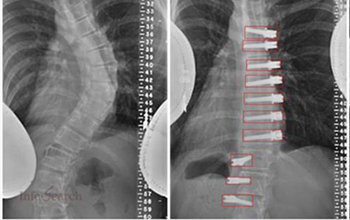

Infosearch collaborated with a medical and educational oriented organization to provide high-accuracy annotation services their applications. The project aimed at annotating the components of the human eye and surgical equipment as key points, which could be further used in medical practice, training clinical assistants, analyzing medical images, and creating healthcare AI models.

The client works within the healthcare and medical technology framework, where annotated datasets are used to improve the learning platforms, increase the diagnostic accuracy, and assist with advanced analytics. Accuracy, knowledge of the domain, and compliance with the healthcare standards were the key success factors of this engagement.

Infosearch offered end-to-end services of key point annotation, user-friendly to healthcare needs. The scope of work included:

Infosearch put trained annotation specialists who were exposed to healthcare datasets into place, using annotation manuals and medical reference materials.

In this case study, Infosearch is depicted as having the ability to provide domain-specific healthcare annotation services, which are based on medical knowledge and strong quality procedures. The effective annotation of the eye anatomy and surgical equipment parts supports the role of Infosearch as a reliable partner in healthcare data and analytics support.